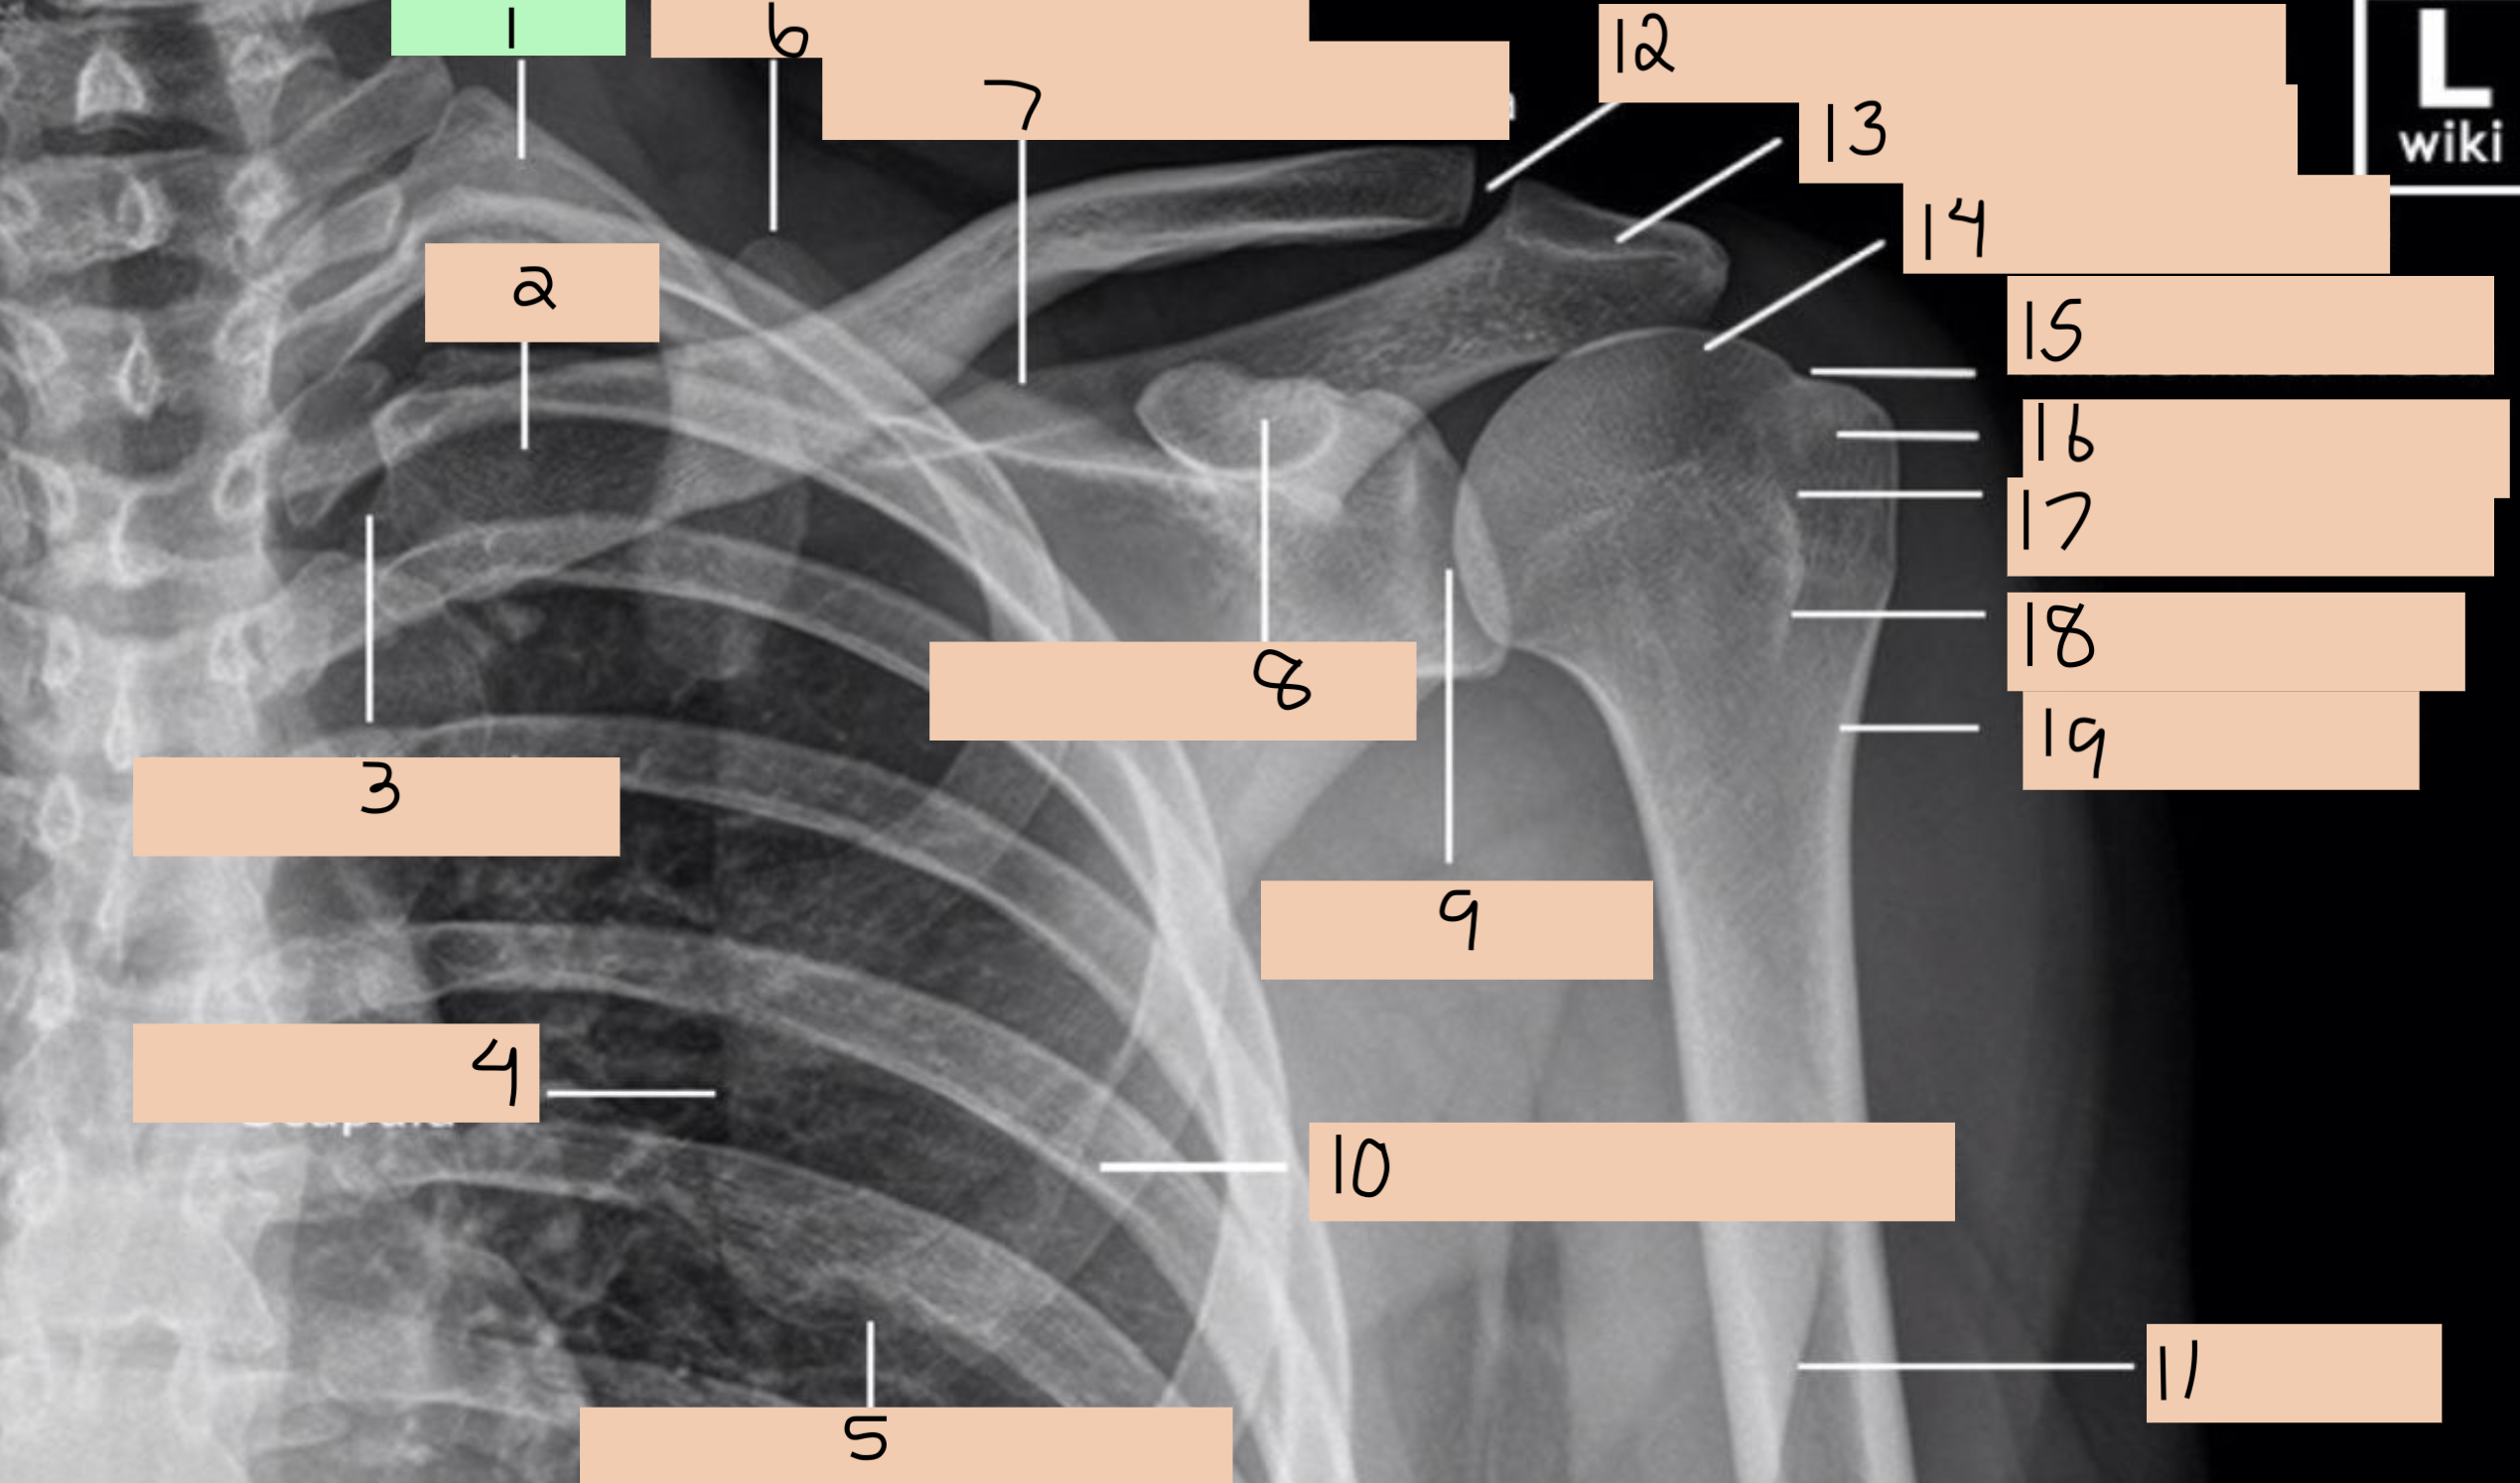

1

1st rib

2

clavicle

3

sternoclavicular joint

4

medial border scapula

5

inferior angle scapula

6

superior angle scapula

7

superior border scapula

8

coracoid process

9

glenoid fossa

10

lateral border scapula

12

acromioclavicular joint

13

acromion process

14

head of humerus

15

anatomical neck

16

greater tubercle

17

intertubercular groove

18

lesser tubercle

19

surgical neck